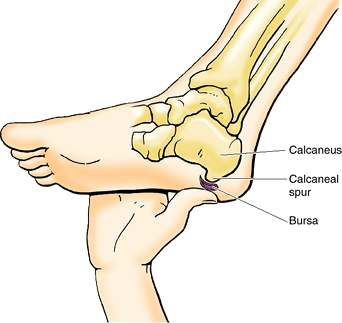

A calcaneal fracture is usually disabling because it disrupts the

subtalar (talocalcaneal) joint, where the talus articulates with the